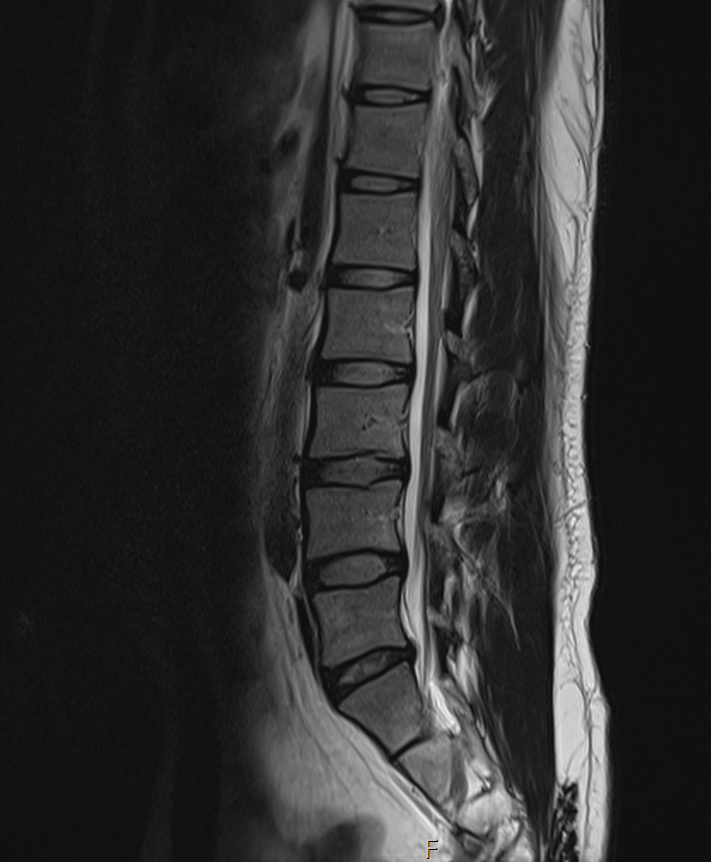

현재

• 2번 째 사진

1년 전 사진에 비해 허리디스크 상황이 악화된 것으로 생각됩니다. 다리저림은 이로 인한 증상으로 생각됩니다.

그러나, 말씀하신 내용과 검사결과만으로는 교통사고와의 연관성에 대해 단정지어 말하기는 어렵습니다. 증상이 점차 악화되어 발생한 것인지, 교통사고에 의해 갑자기 악화된 것인지에 대한 판단이 추가로 필요하겠습니다.